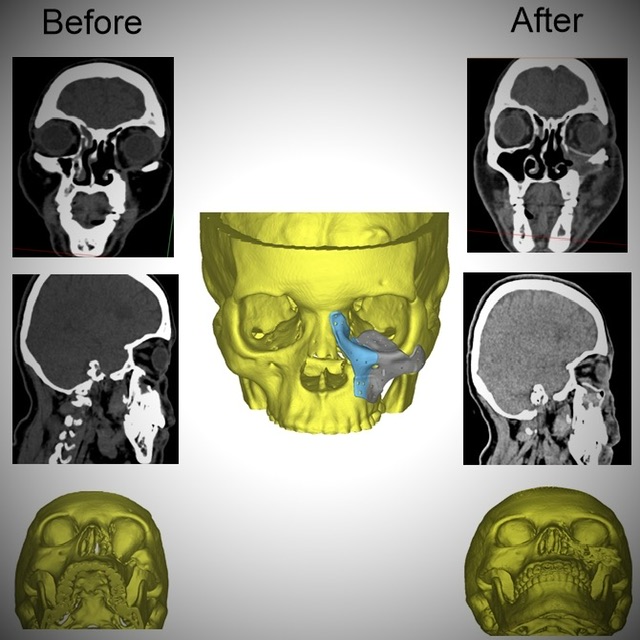

وقال بيان لهيئة الرعاية الصحية، إن السيدة جاءت للمستشفى وهي تعاني من تسوس وتآكل بعظام الوجه وحجاج العين مما استدعى مثول السيدة للعديد من الجراحات التي أدت في النهاية لتشوه عظام الوجه على مدار 4 سنوات من المعاناة، وفقدت السيدة الأمل في مواجهة تحديات كبيرة نتيجة تشوه الوجه ورفض الكثير التدخل الجراحي.

وأضاف البيان، أن قسم جراحة الوجه والفكين بمستشفى الكرنك الدولي اتخذ القرار الطبي بعد استقرار حالة المريضة والمتابعة المستمرة للتأكد من إمكانية التدخل باستخدام التقنيات الحديثة لإعادة البسمة والأمل والثقة للسيدة في علاج التشوه الشديد بالوجه.

وأشار البيان إلى استخدم القسم تصميم معقد مصنوع من مادة الـpeek والمستخدمة حديثًا في استيعاض عظام الوجه وذلك من خلال جراحة دقيقة استغرقت حوالي 6 ساعات.